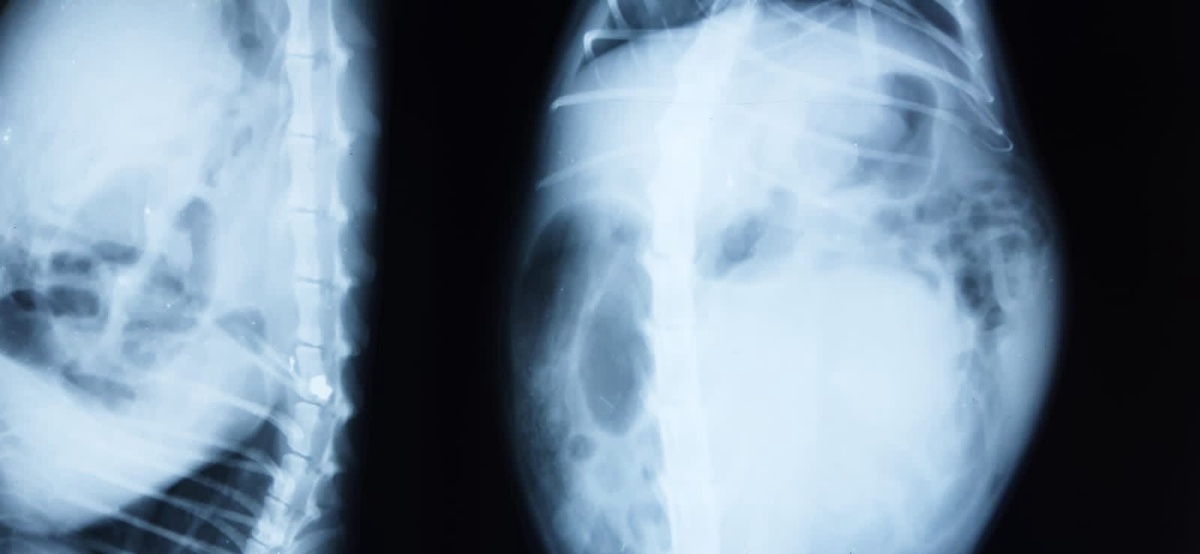

пуля в позвоночнике